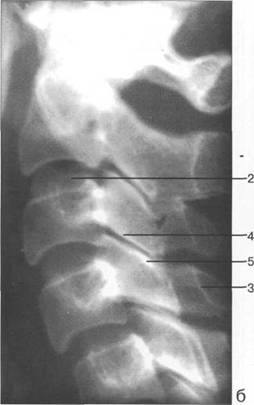

К моменту рождения (рис. 3.1) тело позвонка почти полностью состоит из к 141s183b 86;стной ткани, за исключением лимбусов, которые остаются хрящевыми. Дуга представлена двумя половинами, не слившимися ни с телом позвонка, ни между собой. Суставные отростки сохраняют перифе